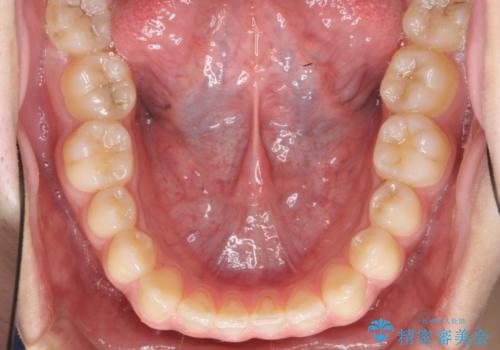

前歯のすきま 受け口 インビザラインで

治療症例の内容

- 治療計画

- 前歯のすき間を気にして来院。

受け口もあり、前歯が端同士であたる、切端咬合となっていました。

下の歯のすき間を閉じて上の歯の内側に入るように位置付けました。

すき間もきれいに閉じ、満足していただきました。

上の前歯は下の歯と直接へりが当たっていた状態(切端咬合)だったため、形がいびつだったのは、わずかにやすりがけをして整えました。

セラミックですき間を閉じようとすると、すきまをうめるために巨大な歯になり、また、下の歯が前に出て強く当たるため、セラミックがかけるおそれがあります。また、下の歯をさけようとすると角度をかえるために歯を極端に削らなければならなくなり、神経をとらなければいけなくなるリスクもあります。

このような歯並びは、セラミックでかぶせるよりは、矯正治療の

適応と言えます。